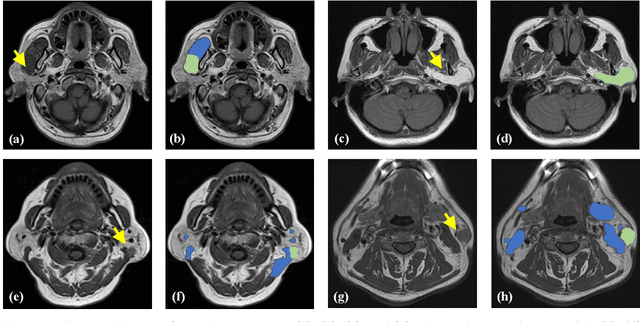

Abstract:Magnetic Resonance Imaging (MRI) plays an important role in diagnosing the parotid tumor, where accurate segmentation of tumors is highly desired for determining appropriate treatment plans and avoiding unnecessary surgery. However, the task remains nontrivial and challenging due to ambiguous boundaries and various sizes of the tumor, as well as the presence of a large number of anatomical structures around the parotid gland that are similar to the tumor. To overcome these problems, we propose a novel anatomy-aware framework for automatic segmentation of parotid tumors from multimodal MRI. First, a Transformer-based multimodal fusion network PT-Net is proposed in this paper. The encoder of PT-Net extracts and fuses contextual information from three modalities of MRI from coarse to fine, to obtain cross-modality and multi-scale tumor information. The decoder stacks the feature maps of different modalities and calibrates the multimodal information using the channel attention mechanism. Second, considering that the segmentation model is prone to be disturbed by similar anatomical structures and make wrong predictions, we design anatomy-aware loss. By calculating the distance between the activation regions of the prediction segmentation and the ground truth, our loss function forces the model to distinguish similar anatomical structures with the tumor and make correct predictions. Extensive experiments with MRI scans of the parotid tumor showed that our PT-Net achieved higher segmentation accuracy than existing networks. The anatomy-aware loss outperformed state-of-the-art loss functions for parotid tumor segmentation. Our framework can potentially improve the quality of preoperative diagnosis and surgery planning of parotid tumors.